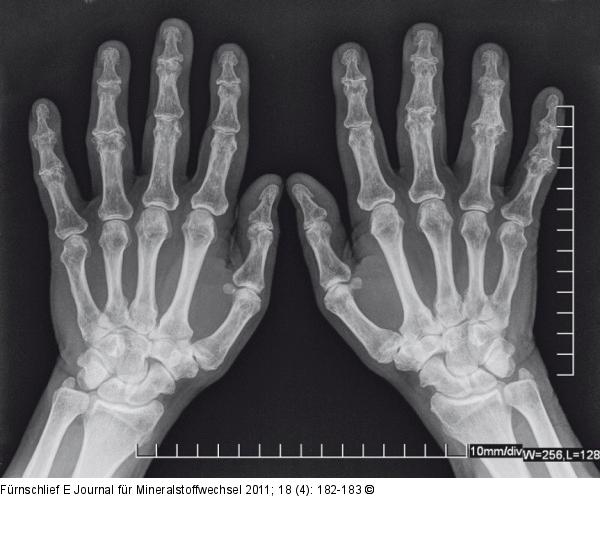

Abbildung 1: Arthrose Vor bzw. während der Behandlung |